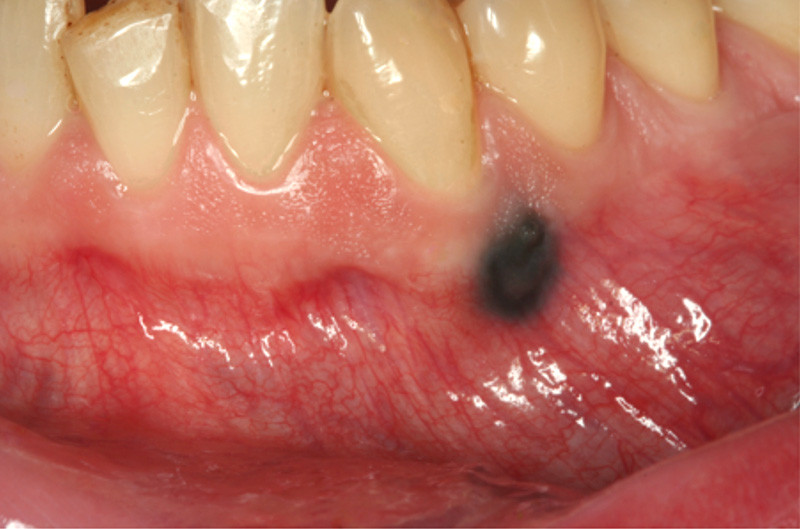

Motif de la consultation. Patient de 42 ans, inquiet après la découverte d’une macule gingivale vestibulaire noirâtre.

Histoire de la maladie. Ce patient, qui est médecin interniste, a observé fortuitement cette macule noirâtre et sa couleur lui fait suspecter un mélanome.

Examen clinique. On observait une macule noirâtre, à surface plane, arrondie, de 5 mm de diamètre, à limites nettes, qui siégeait à cheval sur la gencive attachée et la gencive libre, à hauteur de la dent 33. Les limites étaient nettes et régulières, et la teinte presque homogène. Il n’y avait pas d’autre lésion cutanéo-muqueuse.